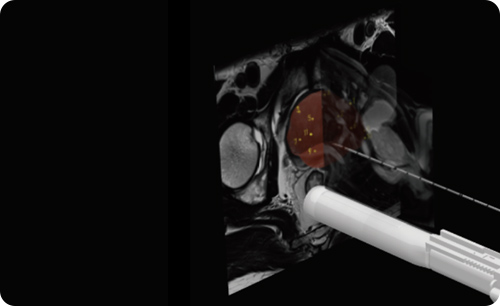

Sensitive magnetic sensor to connect Ultrasound probe.

12 holes in 6 colors for better recognition and easy access.